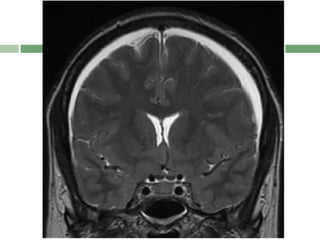

 E- Enhancement of the pachymeninges

Acronym : SEEPSfor MRI Features  SEEPS  S- Subdural fluid collections  E- Enhancement of the pachymeninges  E- Engorgement of the venous structures  P- Pituitary enlargement  S- Sagging of the posterior structures